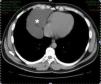

Computed tomography (CT) scan (Figure 2) showed a large well-defined mass 11.2 cm × 7.4 cm in diameter projecting into the right costophrenic angle, suggesting a diagnosis of pericardial cyst or bronchogenic cyst.